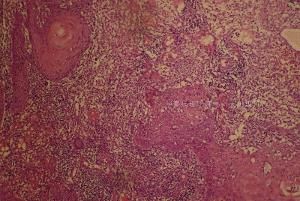

脂溢性角化病根據組織病理有3種類型:角化型、棘層肥厚型和腺樣型

1.角化型

以角化過度和乳頭瘤樣增生較為顯著棘層肥厚較輕,並且由於角質內陷多有假性角質囊腫形成。黑素增多不明顯。

2.棘層肥厚型

以棘層肥厚最為顯著而角化過度和乳頭瘤樣增生較輕有時亦可見假性角質囊腫,偶爾可見真正的角質囊腫。黑素多少不一。

3.腺樣型

由多數細束條狀表皮細胞組成束條相互交織成網並分支,似腺體。黑素增多。

組織病理檢查,可見表皮角化過度、棘層肥厚和乳頭瘤樣增生。